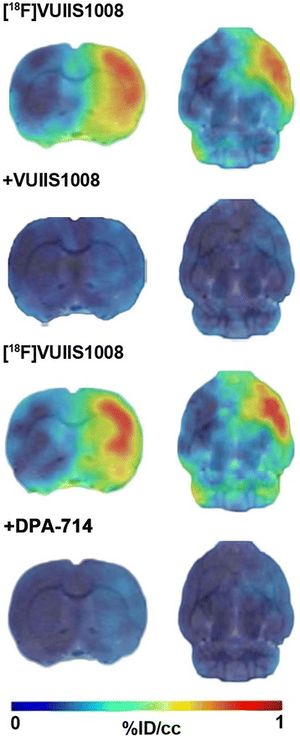

Comparison of Diffusion-Weighted MRI Reconstruction methods for Visualization of Cranial Nerves in Posterior Fossa Surgery

Publication: Front Neurosci. 2017 Oct 9;11:554. PMID: 29062268 | PDF Authors: Behan B, Chen DQ, Sammartino F, DeSouza DD, Wharton-Shukster E, Hodaie M. Institution: Division of Brain, Imaging and Behaviour - Systems Neuroscience, Krembil Institute, University Health Network, Toronto, ON, Canada. Abstract: Diffusion-weighted imaging (DWI)-based tractography has gained increasing popularity as a method for detailed visualization of white matter (WM) tracts. Different imaging techniques, and more novel, advanced imaging methods provide significant WM structural detail. While there has been greater focus on improving tract visualization for larger WM pathways, the relative value of each method for cranial nerve reconstruction and how this methodology can assist surgical decision-making is still understudied. Images from 10 patients with posterior fossa tumors (4 male, mean age: 63.5), affecting either the trigeminal nerve (CN V) or the facial/vestibular complex (CN VII/VIII), were employed. Three distinct reconstruction methods [two tensor-based methods: single diffusion tensor tractography (SDT) 3D Slicer, eXtended streamline tractography (XST), and one fiber orientation distribution (FOD)-based method: streamline tractography using constrained spherical deconvolution (CSD)-derived estimates (MRtrix3)], were compared to determine which of these was best suited for use in a neurosurgical setting in terms of processing speed, anatomical accuracy, and accurate depiction of the relationship between the tumor and affected CN. Computation of the tensor map was faster when compared to the implementation of CSD to provide estimates of FOD. Both XST and CSD-based reconstruction methods tended to give more detailed representations of the projections of CN V and CN VII/VIII compared to SDT. These reconstruction methods were able to more accurately delineate the course of CN V and CN VII/VIII, differentiate CN V from the cerebellar peduncle, and delineate compression of CN VII/VIII in situations where SDT could not. However, CSD-based reconstruction methods tended to generate more invalid streamlines. XST offers the best combination of anatomical accuracy and speed of reconstruction of cranial nerves within this patient population. Given the possible anatomical limitations of single tensor models, supplementation with more advanced tensor-based reconstruction methods might be beneficial. |

Reconstruction methods differ in how they represent underlying diffusion processes. (1) Axial view of a sample tensor map displaying CN V entry into the brainstem, (2) Tensors visible as glyphs displaying CN V entry into the brainstem, (3) results from single diffusion tensor tractography (SDT) after placing region-of-interest (ROI) seeds on anterior portions of CN V bilaterally. Generated streamlines do not show their projections to brainstem nuclei, (4) results from EXtended Streamline Tractography (XST) after placing ROI seeds on anterior portions of CN V bilaterally. Streamlines projecting to the area of the nuclei of the trigeminal nerves can be seen, (5) Axial view of sample fiber orientation distribution (FOD) map displaying CN V entry into the brainstem, (6) results from streamline tractography on FODs derived from constrained spherical deconvolution (CSD) after placing ROI seeds on anterior portions of CN V bilaterally. Streamlines projecting to the area of the nuclei of the trigeminal nerves can be seen. |